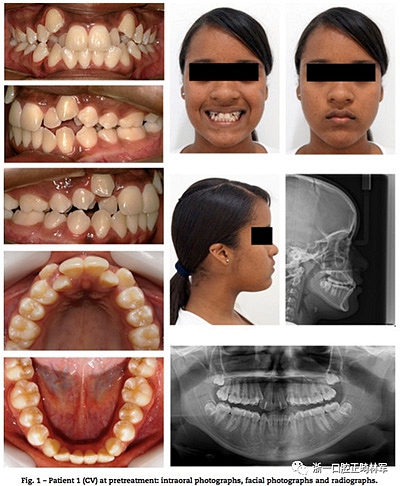

一、患者信息

13歲雙胞胎女性患者,安氏II類錯合畸形伴嚴重上頜牙列擁擠,異位尖牙。臨床檢查提示雙胞胎患者情況類似,如:側貌、長面型、中等頰廊及唇肌松弛。不同點有:一名表現(xiàn)為露齦笑,右上頜側切牙空間不同(圖1,2),頭影測量指標見表1。